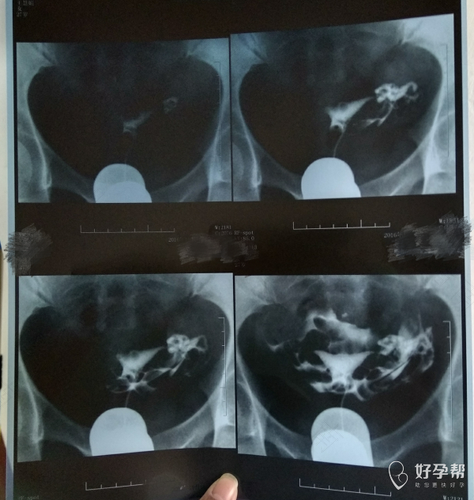

首先,子宫输卵管造影损伤小,准确率高,是临床上应用较为广泛的方法之一。检查完后也可以较快恢复,还可以顺便治疗轻微的炎症。造影使用的是数字X光机,有清晰的显像,可以确定具体的堵塞位置和性质。另外还可以顺便检查是否有其他妇科疾病。